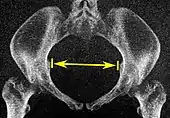

| Pelvic outlet | Sagittal pelvic outlet diameter | ![]() |

Same, but may require minor side-to-side scrolling to visualize both end points. | The closest bony points of the sacrococcygeal joint and the pubic bone next to the symphysis. This is also called the obstetric anteroposterior diameter of the pelvic outlet, to distinguish from the anatomic one which includes the coccyx.[7] However, the coccyx is normally pushed away during childbirth by laxity in the sacrococcygeal joint.[8] | 9.5 to 11.5 cm.[6] |